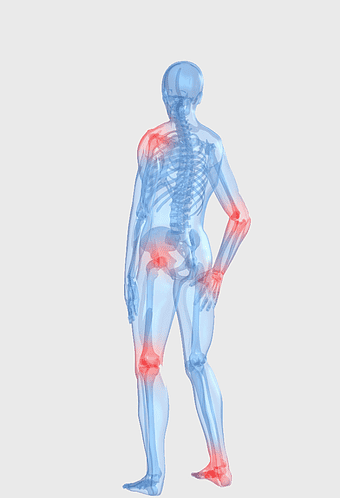

rheumatoid arthritis illustration, chronic pain therapy, joint replacement surgery, blue violet human skeleton, skeletal anatomy diagram, arthritis pain relief methods, orthopedic health visual aids -

arthritis pain symptoms, rheumatoid arthritis illustration, joint pain areas, human body anatomy, skeletal health issues, medical visualization, chronic joint discomfort -